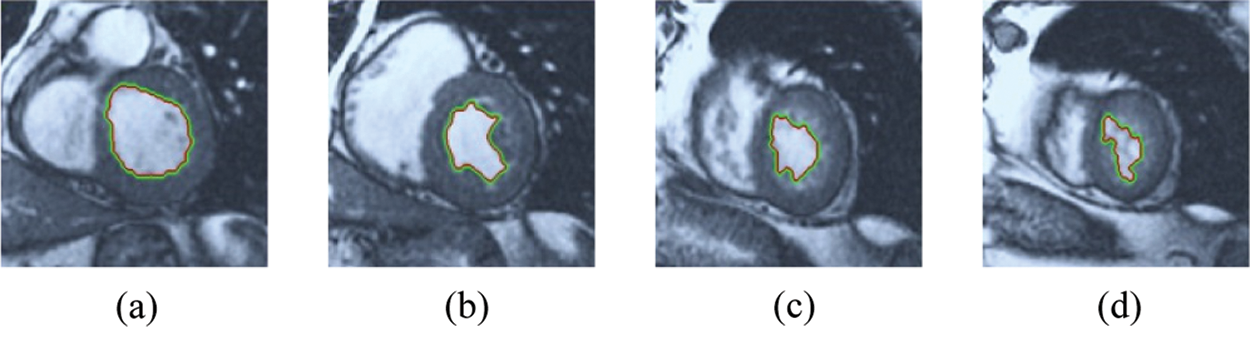

The BRW, HSRW, and ERW medical imaging segmentation schemes are executed on MATLAB, and examined on a short-axis of 3D multi-slices CMRI dataset [27]. Several segmentation performance metrics are utilized such as Dice Metric (DM), the Haussdorff distance (HS), and the Peak signal to noise ratio (PSNR). The BRW, HSRW, and ERW segmentation schemes are executed on a short-axis of 3D multi-slices CMRI datasets. The same multilayer CMRI dataset is segmented using various random walk methods. The presented results were obtained through using BRW, HSRW and ERW methods on five different groups of patients; each group contains 25 subject of multilayer CMR dataset. Experimental results illustrate that the BRW method can achieve a good segmentation of the LV cavity. The results of the HSRW algorithm have very comparable similarities to BRW, but with a slightly less efficiency and a much higher execution rate. Pre-calculations reduce the performance online time in offline mode. The average time of HSRW equals to 0.09 seconds for each slide. Raising the rate of K will improve the comparison and makes the process of segmentation more precise, but also reduces the execution time. The ERW technique results illustrate that this method has the greatest efficiency of segmentation. Figs. 5 to 7 show the resulting images of the BRW segmentation method on five sets of sample data. HSRW with pre-calculation segmentation method is applied on the same sets of sample data and illustrated in Figs. 8 to 10. Figs. 11–13 show the high efficiency segmentation using the ERW method with an earlier model for the same sets of sample data. The results of the Random Walk segmentation overcame the potential restrictions of the prior art CMR methods. The performance of segmentation is fast compared to segmentation methods based on edge and region. BRW precedes into account the properties of regions and edges, as shown in Figs. 5–7. Looking at the image as a graph, the technique makes it possible to integrate pixel relations with neighboring pixels. As a result, segmentation produces good quality BRW technique sections when their qualitative accuracy is compared to the ground truth, and this is also evident from the Tab. 1 measurements in the diastolic and systolic phases in Tab. 2 as well as in the complete cardiac cycle noticed. Figs. 8–10 illustrate the HSRW results. There are no dissimilarities observed in furthermost cases of CMR slides in the figures, but the correspondence measurements of the DM, PSNR and HS coefficients present that the results of the HSRW technique are worse than those of the BRW method. This presents that HSRW is an effective estimation of the random walk influence as mentioned in Tab. 1 and throughout the cardiac cycle in Tab. 2. The values of PSNR and DM are lower, whereas HS is higher than the BRW method, but with slight dissimilarities between HSRW and BRW methods throughout the blood circulation. The impact of execution eigenvectors pre-calculations is perfect when the execution time is faster than the BRW method and, in fact, more efficient than other segmentation method for LV heart segmentation. With the identical dataset, the ERW method shows a significant enhancement in efficiency, as presented in Figs. 11–13. From the scores, we can see that the segmentation is smoother and cleaner. The ERW method considers boundaries and areas, such as BRW, using the relations between adjacent pixels in the image. It also considers the additional regional advantage by including the assumptions that affect the results of the segmentation. Mean segmentation quality measurements are computed from the segmented images using correspondence measurements for instance DM, HS, and PSNR and verified for each method in the diastolic and systolic stages as presented in Tab. 1. Based on results, it can be determined that methods of random walk are enhanced in diastolic diagnosis and that their outcomes in the systolic stage are also of good efficiency. The results of the random walk segmentation methods in the complete blood circulation are shown in Tab. 2. The cardiac cycle similarity amounts indicate that DM and PSNR capacities of ERW are improved than the corresponding capacities in the case of the HSRW and BRW approaches; however, the HS measurements are lower than the equivalent measurements, as illustrated in Tab. 2. This designates that the ERW technique is the furthermost accurate segmentation technique among all the approaches stated above. The ERW technique has the uppermost value of PSNR, and the HSRW method has the lowermost value that denotes the uppermost speed in segmentation process.

Figure 5: BRW results for the first samples set

Figure 6: BRW results for the second samples set

Figure 7: BRW results for the third samples set